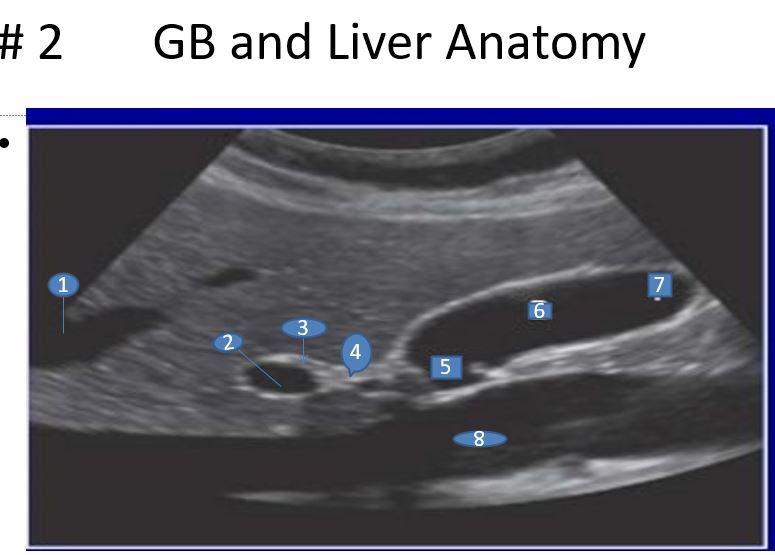

1. Left Hepatic Vein

2. Portal Vein

3. Common Bile Duct

4. Cystic Duct

5. Neck

6. Body

7.Fundus

8. Inferior Vena Cava (IVC)